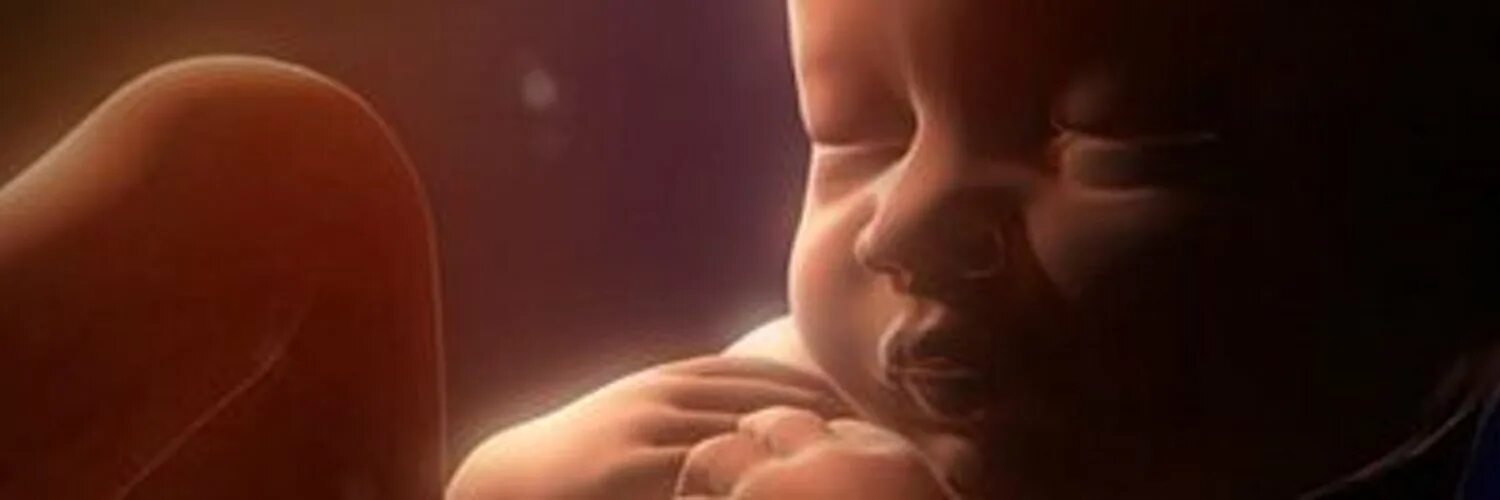

Ребенок 36 недель беременности в животе